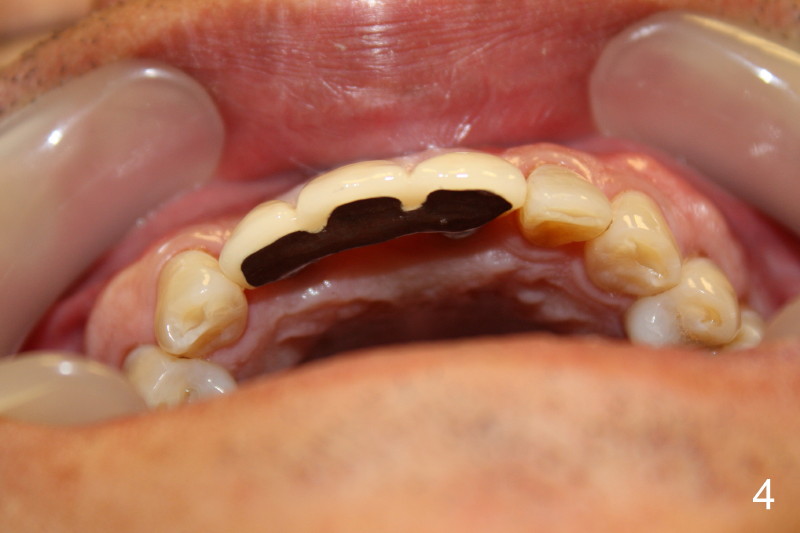

This time PFM FPD was fabricated with lingual metal as shown in Fig.4. The bridge was temporarily cemented on Feb. 09, 2011. Night guard was fabricated later. Unfortunately the bridge came off 7 months later and was recemented temporarily. Permanent cementation was not attempted, because of potential porcelain chip or implant/abutment screw loosening due to bruxism. Yesterday, the patient reported that the bridge was loose again. Today, #7 build-up changed from loose, disintegrated Cavit to more solid composite (Fig. 5 to 6). The bridge was cemented temporarily to avoid porcelain chip related to permanent rigid cementation. Fig.7 shows occlusal equilibrium after cementation. The patient felt that there was no premature contact to the bridge. What should we do next? Can we add an implant at the site of #8. Can this alleviate bruxism-related problems (easy decementation, porcelain chip and possible loosening of screw between abutment and implant)? Thanks.